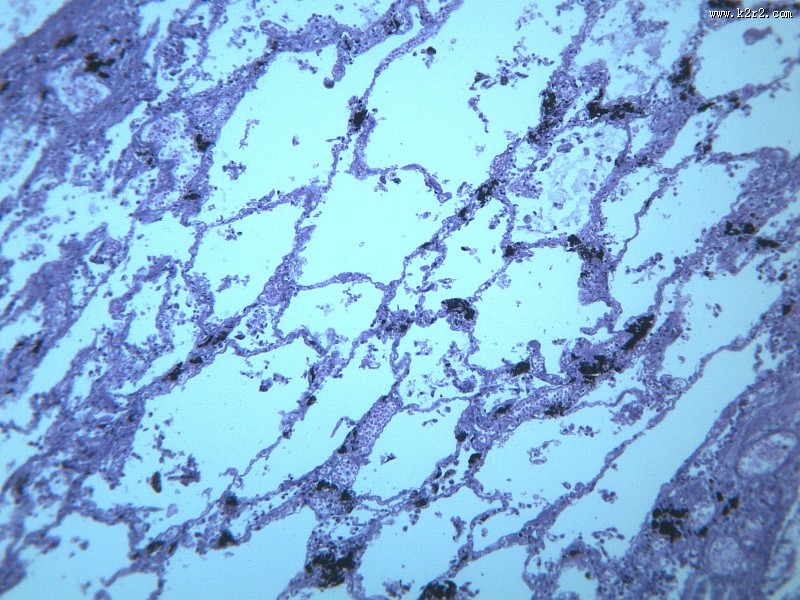

慢性支气管炎 - 第11张

慢性支气管炎

显微切片

chronic bronchitis

支气管炎